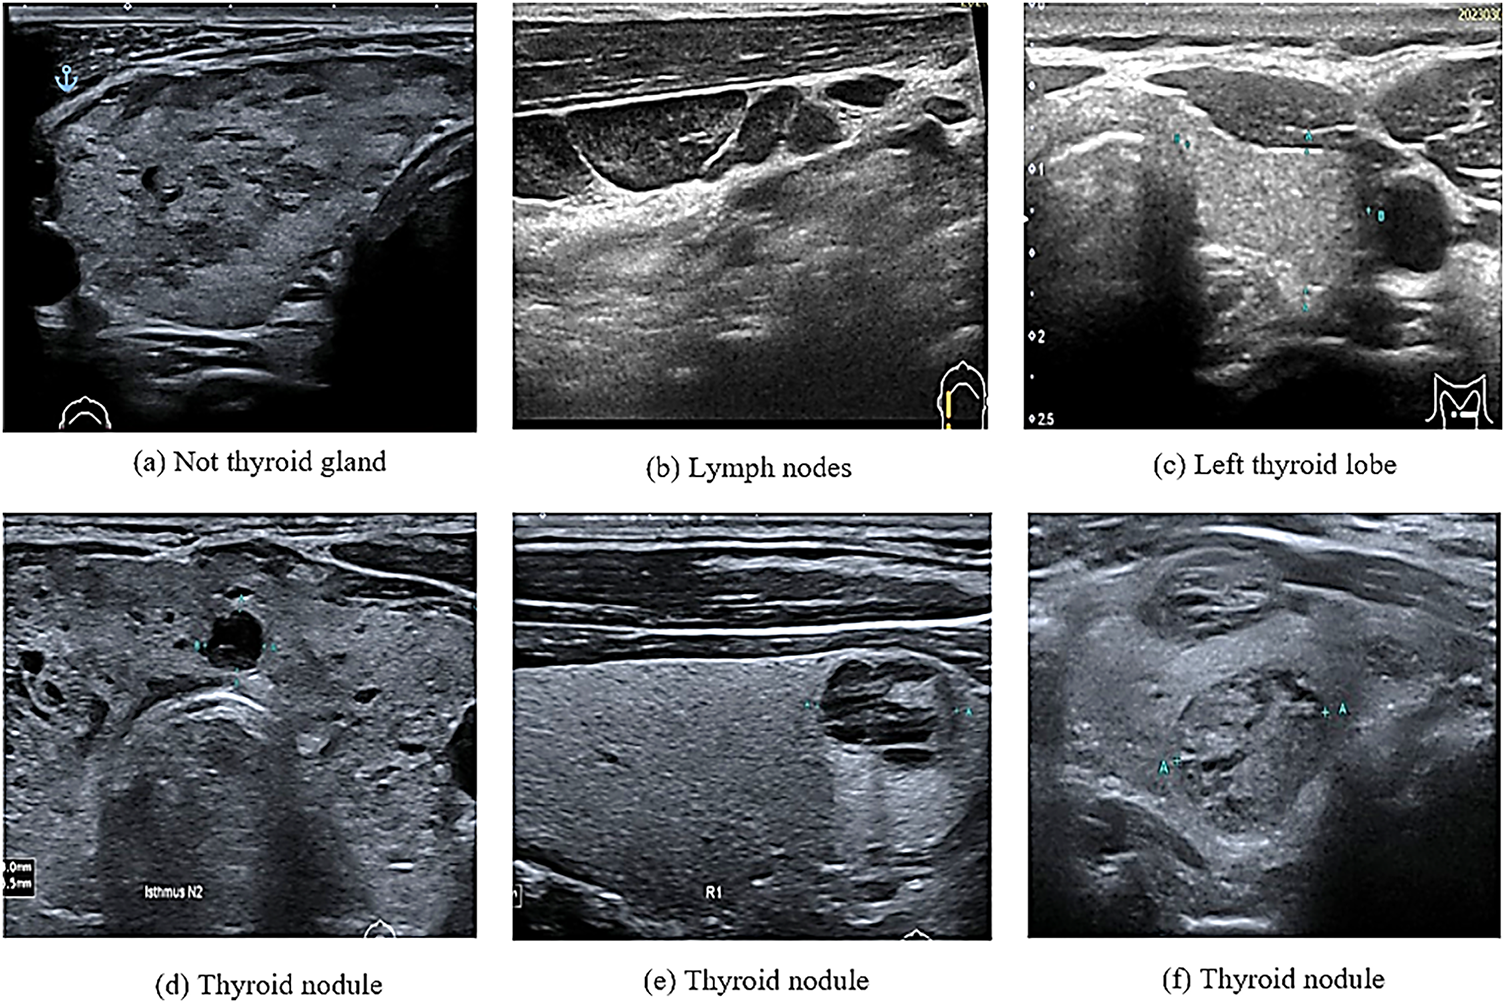

In computational biology, patient data collection is essential for disease prediction. This can be achieved by selecting features from multiple datasets that are easily distinguishable in healthy individuals. In contrast, selecting the wrong features could lead to the unnecessary treatment of healthy individuals [1]. In recent years, various computational methods have been applied to medical images for the prediction and solution of complex problems. For example, such methods have been used in the detection and diagnosis of thyroid nodules that grow abnormally in the thyroid gland. These nodules affect the normal function of the thyroid gland in the secretion of essential hormones. This, in turn, affects the protein synthesis and metabolism rates [2,3]. The number of thyroid nodule diagnoses and the number of patients with thyroid nodule cancer, especially among women under 30 years old, have increased in recent years [4]. For this reason, the accurate and efficient detection of suspicious thyroid nodules, which relies on radiologists’ experience and skills, is highly important [5]. The detection of thyroid nodules is often performed using various methods such as computed tomography, magnetic resonance imaging, and ultrasound imaging. Among these methods, ultrasound imaging is the most commonly used because it is safe and affordable [5]. Coinciding with the development of artificial intelligence (AI) technology, computer-assisted diagnostic systems have been increasingly used in the medical field [6]. However, in medical imaging, a major issue associated with these technologies is the similarities among different image categories and the differences in images of the same category [7]. For example, as shown in Fig. 1, these images may contain thyroid nodules, lymph nodes, the left thyroid lobe, or the thyroid gland. This is particularly noticeable in ultrasonography, which mainly relies on the doctor’s experience in interpreting these images and diagnosing thyroid diseases [8].

Figure 1: Ultrasound thyroid images (a–c) images without thyroid nodules (d–f) images with thyroid nodules